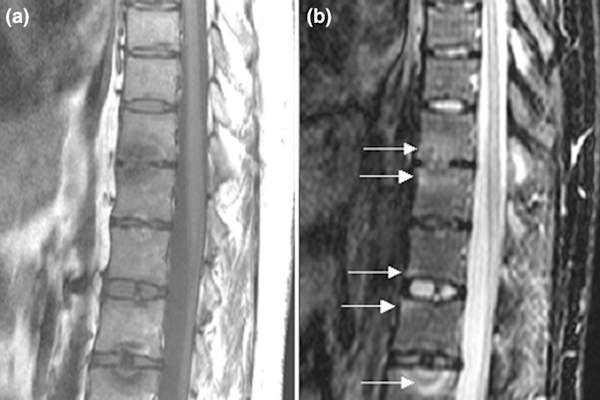

背部和臀部活动能力有限

大约20%患有银屑病关节炎的人会发展成银屑病脊柱炎,这是一种会导致颈部和脊柱不适的病症。早期症状包括腰背部或臀部疼痛或僵硬,根据梅奥诊所。但是...背痛可能意味着上百万的东西,对不对?PsA的相关联的类型经常醒来或不活动的周期以后起床后发生。

不良姿势

如果脊柱炎的炎症得不到控制,就会导致一种被称为强直性脊柱炎在这里,椎骨完全融合,如果你试图挺直,就会导致驼背的姿势和疼痛。